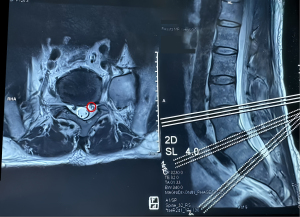

A 51-year-old male complained of radiating pain in the left buttock and left lower limb for 3 months. He was diagnosed with lumbar disc herniation in two other hospitals. Both of them suggested surgical treatment, which the patient refused. The findings from physical examination were as follows: positive sign on Kernig’s test, which induced pain at 60°; grade V left lower-limb myodynamia accompanied by numbness and pain in the left buttock, radiating to lateral aspect of the left thigh and calf; and a Visual Analogue Scale (VAS) score of 7. MRI showed left side nerve root edema in the L4–L5 segment but no obvious disc herniation (Figure 1).